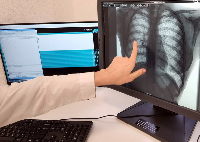

Любого доктора можно быстро подготовить как рентгенлаборанта и дать необходимые знания для оценки рентгенограмм.

Изучение проблемы низкого качества рентгенограмм на Вашем оборудовании.